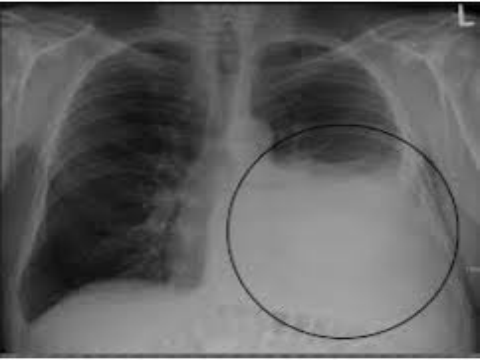

Đặc điểm hình ảnh học Xquang cắt lớp điện toán u mô đệm đường tiêu hóa